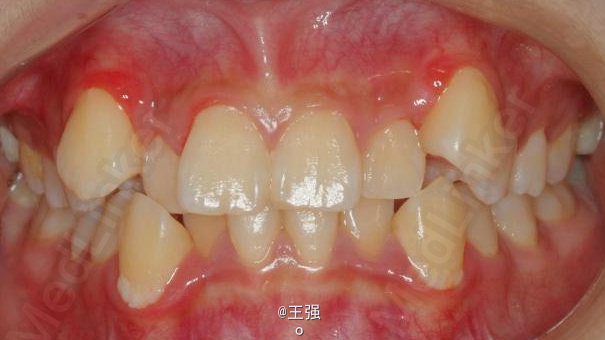

在临床上,我们常常会遇到亚类病例,对于亚类病例,有时需要不对称拔牙,常见的不对称拔牙方法有:上颌对称,下颌数目对称但是位置不对称。还有上颌对称,但是下颌数目不对称。其目的就是为了取得尽可能理想的尖窝对应咬合关系 该病例右侧是中性关系,左侧是中性偏远中关系,上颌中线正,下颌中线左偏约1mm。左侧磨牙关系距离中性关系约差2mm左右。如果采用对称性拔除下颌左右四,我们面临的问题是,一、如何保证矫治后上下中线一致,二、如何保证左侧磨牙关系矫治后为中性关系。治疗过程中势必会用到不对称牵引。我个人认为除非是功能性的因素,矫治过程中最好不要用不对称牵引。 关于中线和磨牙关系的问题,我认为应在矫治计划制定时就应考虑到,而不是等到矫治第三阶段所谓精细调整阶段再来解决。事实上到了这个阶段采用了不对称的牵引,即使暂时取得了中线对齐的矫治目的也是不稳定的。 这个病例,用了不对称的拔牙,右下拔四,左下拔五。下颌牙齿在漂移的过程中(几乎没有外来力量),下前牙自然就会向右比向左多漂移一些,中线在下颌还没有开始矫治时就对齐了,左下六因没有五的存在,自然就向近中多漂移一些,和上颌六形成中性关系。接下来的矫治就会非常简单,而结果自然也非常稳定。